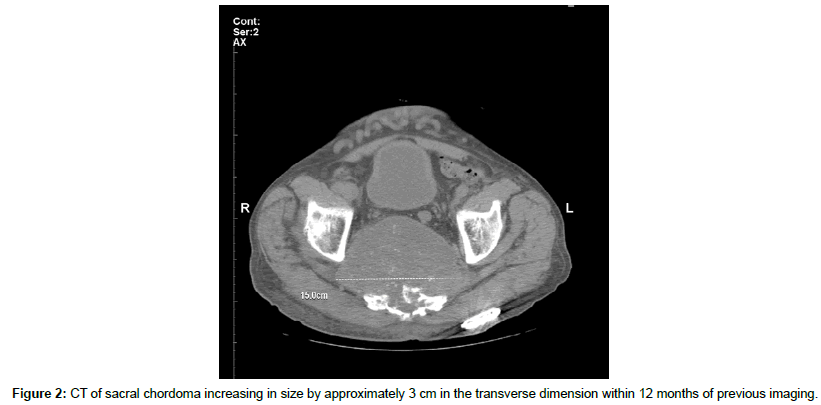

Imaging included a CT of the bony pelvis, which demonstrated a large sacral chordoma measuring 6.4 cm anterioposteriorly by 9.7 cm transversely by 10 cm sagittally invading the sacral foramen, extending through the right sciatic notch and displacing soft tissue structures within the posterior pelvis (Figure 1). The mass had increased in size by approximately 3 cm in the transverse dimension and to a lesser extent in other dimensions compared to a previous CT completed 12 months prior (Figure 2). Distention of the urinary bladder consistent with urinary retention was also described.

The patient’s postoperative course was unremarkable and he was discharged to home. At his two-week follow-up appointment, he reported significant improvement in his lower back pain and lower extremity symptoms with decreased opioid analgesic requirements. Over the subsequent months, he developed fecal incontinence and elected for a diverting colostomy, as well as worsening urinary retention and lower extremity and scrotal edema. He did not receive palliative chemotherapy or radiation therapy during this time. A oneyear postoperative CT scan revealed an enlarging sacral chordoma measuring 11.3 cm anterioposteriorly by 15.0 cm transversely by 11.8 cm sagittally. However, the patient continued to report adequate pain control from his SCS.